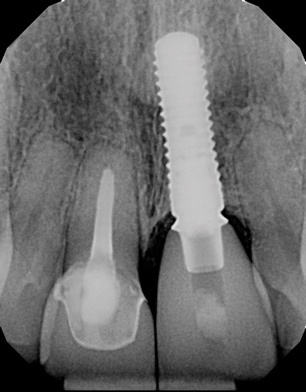

Fig 12. Periapical radiograph at 5 years.

Figure 12

Figure 8 shows the provisionalization of No. 8 at 6 weeks postoperatively and a screw-retained provisional restoration on No. 9 to develop the subgingival transitional zone (key Nos. 8 through 10). The transitional zone will be duplicated using the custom impression coping technique. Figure 9 and Figure 10 depict the completed crowns at 5 years; implant No. 9 was screw-retained (key No. 10). In Figure 10 note the convex contours facial to implant No. 9 that are attributed to the connective tissue grafting as part of the surgical protocol creating biotype conversion from a thick to a thicker biotype. Figure 11 through Figure 13 show 5-year postoperative patient smile, periapical x-ray, and CBCT, respectively.